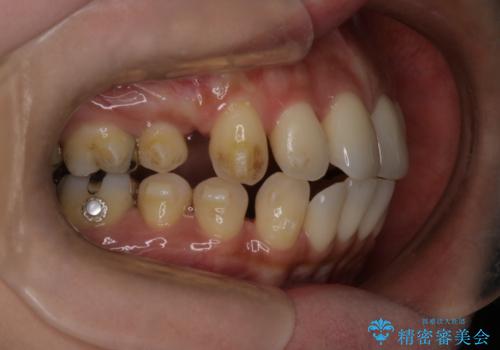

- 上の前歯の突出感を気にして来院された患者様です。

目立たない装置を希望とのことで、上顎左右第一小臼歯を抜歯し、インビザラインにて矯正治療を行うこととしました。

インビザラインにて抜歯矯正を行うと、高頻度で奥歯が咬み合わなくなります。

また、抜歯スペースに向けて奥歯が移動する際、必ず傾斜して移動するため、仕上がりの咬み合わせはワイヤー矯正と比べて明らかに劣ります。

抜歯スペースが閉じてからも咬みにくさ改善のためマウスピース矯正を継続するため、治療期間は長期化します。